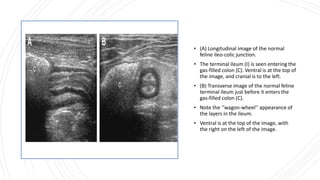

• (A) Longitudinal image of the normal

feline ileo-colic junction.

• The terminal ileum (I) is seen entering the

gas-filled colon (C). Ventral is at the top of

the image, and cranial is to the left.

• (B) Transverse image of the normal feline

terminal ileum just before it enters the

gas-filled colon (C).

• Note the ‘‘wagon-wheel’’ appearance of

the layers in the ileum.

• Ventral is at the top of the image, with

the right on the left of the image.

• (A) Longitudinalimage of the normal feline ileo-colic junction. • The terminal ileum (I) is seen entering the gas-filled colon (C). Ventral is at the top of the image, and cranial is to the left. • (B) Transverse image of the normal feline terminal ileum just before it enters the gas-filled colon (C). • Note the ‘‘wagon-wheel’’ appearance of the layers in the ileum. • Ventral is at the top of the image, with the right on the left of the image.